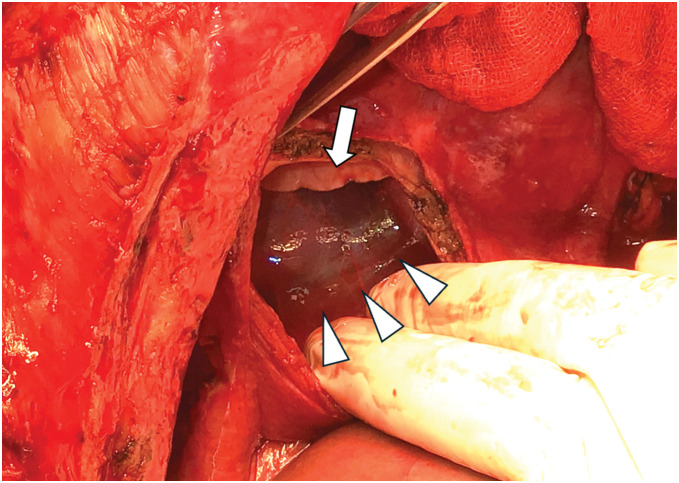

Case presentation: A female patient in her 40s with a history of autosomal dominant polycystic kidney disease presented with progressive liver cyst enlargement (Gigot type III, Qian classification Grade 4), which led to decreased activities of daily living and intracystic hemorrhage. The patient underwent a deceased-donor liver transplantation. During mobilization of the liver from the right side of the diaphragm, the patient experienced sudden onset of pneumothorax. Incision of the diaphragm revealed a cystic structure containing a hematoma, suggesting pneumatocele formation. The pneumatocele was not resected during the ongoing operation; instead, thoracic drainage was performed as the primary intervention. Postoperatively, no air leakage was observed, and the thoracic drain was successfully removed on POD 12. The pneumatocele, which measured approximately 10 × 10 × 7 cm, showed no signs of infection, and was monitored without additional surgical intervention. On POD 19, a fever prompted further evaluation, and CT-guided cyst aspiration for culture was performed, which revealed no evidence of infection. Acute T-cell-mediated rejection was observed on POD 27, and a steroid pulse was administered, but even after that, the pneumatocele gradually decreased in size without any signs of infection.